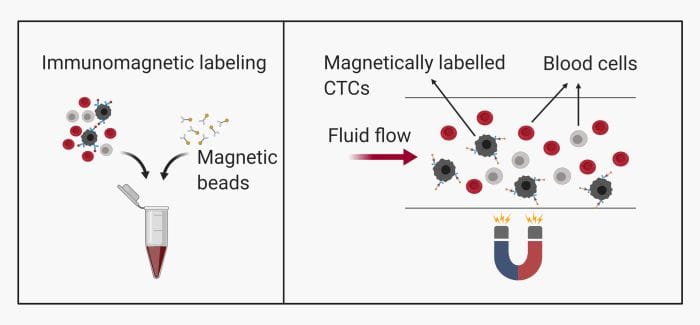

– Immunomagnetic: This method is common and includes labeling the CTCs with magnetic beads. They can then be pulled toward a specific zone on the microfluidics chip using magnets.